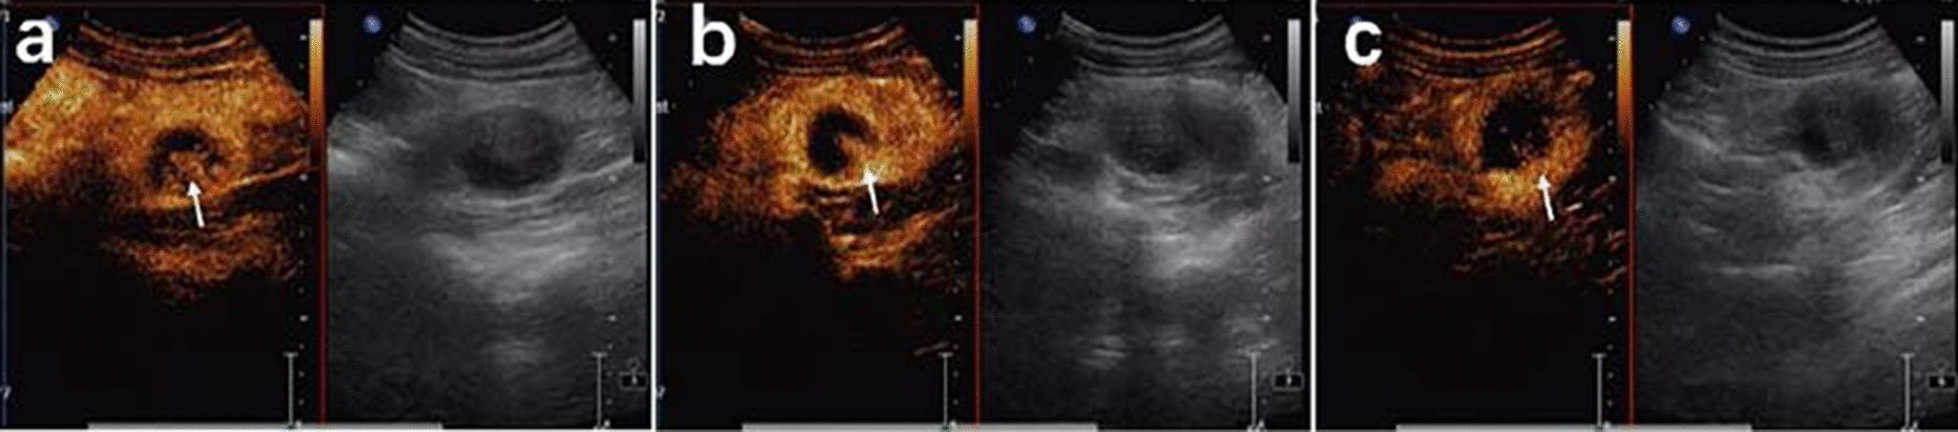

Fig. 1.

CEUS patterns of EWS/pPNET of the kidney in a 20-year-old female patient. a The lesion demonstrates annular enhancement in the cortical phase (arrows). b The lesion showed heterogeneous enhancement in the parenchymal phase (arrow). c The lesion demonstrates simultaneous wash-in with surrounding renal parenchyma in the late enhancement phase (arrow)

A 20-year-old female presented to the hospital with an abdominal mass and gross haematuria for 1 month. She recently complained of left abdominal pain, nausea and vomiting, and noticeable weight loss. The patient did not have a family history of malignant tumours. The physical examination revealed abdominal distention with a large mass in the left upper quadrant. The mass was irregular, hard, immovable, nontender and without overlying skin changes. The laboratory test results for tumour markers were as follows: carbohydrate antigen 125 (CA-125), 136.89 U/mL (reference range: 0.00–35.00 U/ml); the levels of other tumour markers, such as carcinoembryonic antigen (CEA), carbohydrate antigen 199 (CA-199), and alpha-fetoprotein (AFP), were normal. Urine analysis showed that the red blood cell (RBC) count was 56/µl (reference range: 0.0–25.0), and the white blood cell (WBC) count was 59/µl (reference range: 0.0–25.0). Liver and kidney function test results and the complete blood count were within normal levels. Conventional ultrasound (US) examination showed a 4.5 × 3.2 cm irregular lesion at the lower pole of the left kidney. To further clarify the diagnosis of the tumour, contrast-enhanced ultrasound (CEUS) was performed, which presented signs of annular enhancement and heterogeneous enhancement of the tumour, and simultaneous wash-in was predominant. The possibility of a tumour lesion was considered (Fig. 1). A CT scan showed a 3.7 × 3.8 × 4.0 cm heterogeneous mass in the left kidney, which had blurry edges and a high-density dissepiment in the interior. Three-dimensional reconstruction of the kidney showed that the lower one-third of the left kidney was occupied (Fig. 2). Gross total removal of the tumour was achieved. The tumour was a 3.5 × 3 × 2.6 cm well-defined grey‒white nodular mass with necrosis (Fig. 3). Hematoxylin–eosin staining (HE) and immunohistochemistry (Leica DM4 B, DFC7000 T camera and LAS X software) were performed. Under the microscope, the tumour cells were small, round, short spindle-shaped, and densely arranged; Homer Wright rosettes were found; the cytoplasm of the tumour cells was sparse; and the nuclei were slightly enlarged and hyperchromatic. The tumour tissue was accompanied by extensive haemorrhage and necrosis. Immunohistochemistry showed the following: CD99 ( +), Vimentin ( +), EMA (−), CD10 (−), CD56 (−), syn (−), and NSE (−) (Fig. 4). Other immunohistochemistry staining see supplementary information (Additional file 1). The pathological diagnosis was an EWS/pPNET that did not invade the ureters. Subsequently, 21 days after the operation, the patient received 8 cycles of a CAV (vinorelbine, ifosfamide, epirubicin) + IE (isocyclophosphamide, etoposide) regimen from December 1, 2017, to May 11, 2018. Adjuvant radiotherapy (dose: 45 Gy, radiation field: the tumour bed following surgical resection) was also administered from June 11, 2018, to July 13, 2018. At the same time, the serum CA-125 level of the patient showed a gradual downwards trend after surgery and chemotherapy. The serum CA-125 levels returned to normal at the end of chemotherapy and radiotherapy. The patient had no signs of local recurrence or metastasis on CT scan within a follow-up of 4 years.

Imaging methods, such as CT and MRI, have their own specific indications [14] to can help make a correct diagnosis [15]. The EWS/pPNET of the kidney was an inhomogeneous mass with unobvious renal vessels, no signs of invasion, and no calcifications on CT [16, 17]. In a 60-year-old patient with an EWS/pPNET of the kidney, ultrasound revealed an exophytic cortical cyst of the left kidney with irregular echogenic septa. Abdominal MRI and CT scans revealed a large lesion with necrosis of the mass. MRI showed homogeneous hypointensity on T1-weighted images and hyperintensity on T2-weighted images [18]. According to previous literature reports [19–23], we concluded that the CT characteristics of an EWS/pPNET of the kidney are as follows: (1) a large soft tissue mass, (2) the mass can be well defined, (3) necrosis can be found, (4) the renal vein or inferior vena cava may be involved, and (5) calcification is rare. Areas of high density correspond to areas of internal haemorrhage, and areas of low density correspond to areas of necrosis. The CT findings of the patient whose case is presented here are consistent with those previously reported [16–23]. As a radiation-free, inexpensive, and convenient examination method, US can be the primary choice in the diagnosis of EWS/pPNETs. Conventional US may fail to differentiate cystic and necrotic areas due to factors such as resolution. However, CEUS can solve this problem. The EWS/pPNET of the kidney mainly manifested as annular enhancement and heterogeneous enhancement on CEUS, and simultaneous wash-in was predominant in the EWS/pPNET of the kidney. Other common renal malignancies, such as clear cell renal cell carcinomas (ccRCCs), papillary renal cell carcinomas (pRCCs), and chromophobe renal cell carcinomas (chRCCs), can be differentiated from EWS/pPNETs of the kidney on CEUS. ccRCCs are rich in blood vessels, and the vessels of ccRCCs are large, irregular and distorted, with arteriovenous fistulas, which lead to the characteristics of early wash-in and hyperenhancement on CEUS [24]. Furthermore, the rapid tumour growth and proneness to ischaemic necrosis of ccRCCs lead to heterogeneous enhancement. In contrast, pRCCs and chRCCs, owing to the relative lack of vessels or the thick walls of vessels, often show hypoenhancement on CEUS. Previous studies [25] have reported that chRCCs mainly demonstrated simultaneous wash-in, while pRCCs mainly demonstrated slow wash-in. For the wash-out pattern, rapid wash-out mostly appeared in pRCCs and chRCCs. Additionally, EWS/pPNETs need to be distinguished from other uncommon renal tumours, such as adult Wilms, tumours, rhabdoid tumours, and renal clear cell sarcomas. Preoperative diagnosis of these tumours is difficult because there are no specific radiographic findings, and diagnosis relies primarily on histopathology.